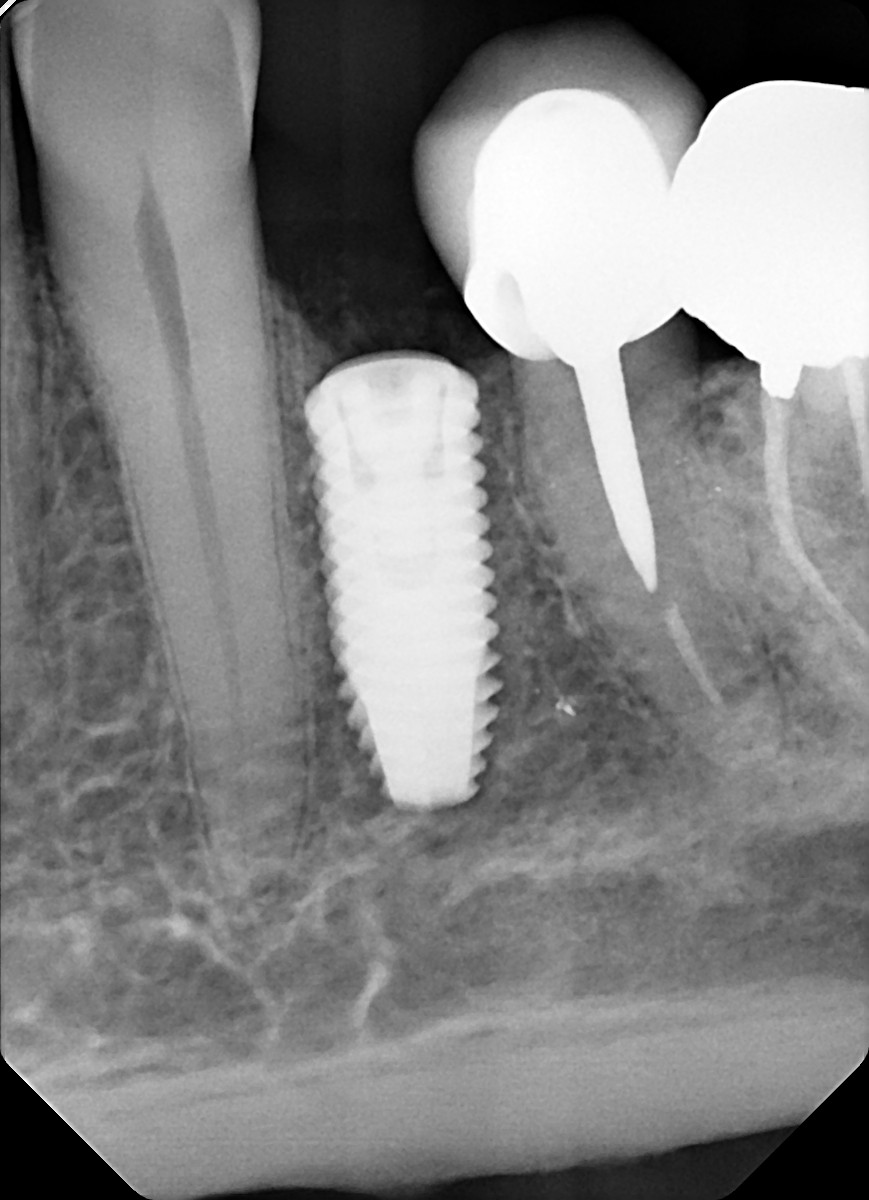

10. What option can explain the restoration on the implant?

22. What option can be selected for the crown over the implant?

25. What option can be selected for the crown over the implant?

28. What option can be selected for the crown over posterior implant?